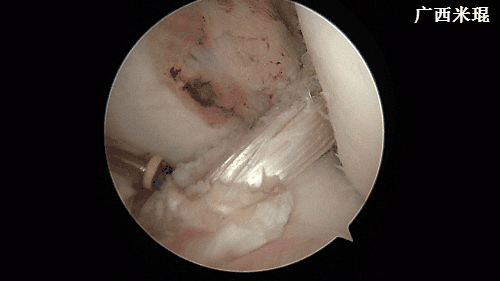

(十七)维合切口

关节镜下检查重建的ACL走向以及张力,屈伸膝关节时观察重建的ACL是否与髁间窝撞击,确认良好后缝合各切口。此过程 一般需要2分钟。